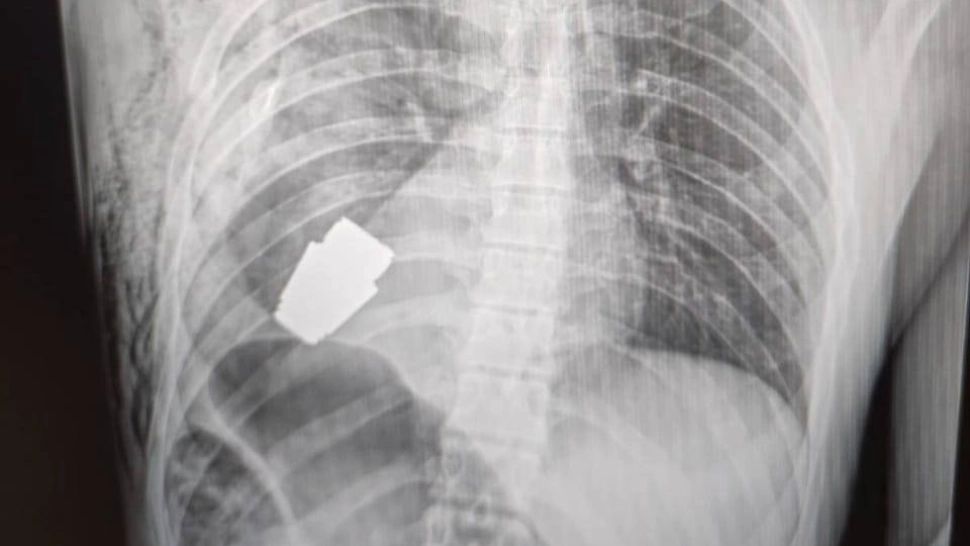

10 ian. 2023, 11:15ExternMedicii militari din Ucraina au scos o grenadă neexplodată din corpul unui soldat